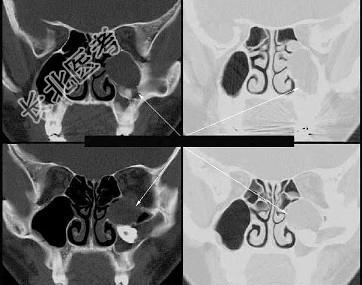

- 多项选择题图为上颌骨囊肿的外观及影像表现,关于此病的描述正确的是 ( )

A、X 线表现为圆形或椭圆形透明阴影

B、生长缓慢,早期无自觉症状

C、囊肿较大时扪之有乒乓球感

D、可引起病理性骨折

E、穿刺可得草黄色囊液